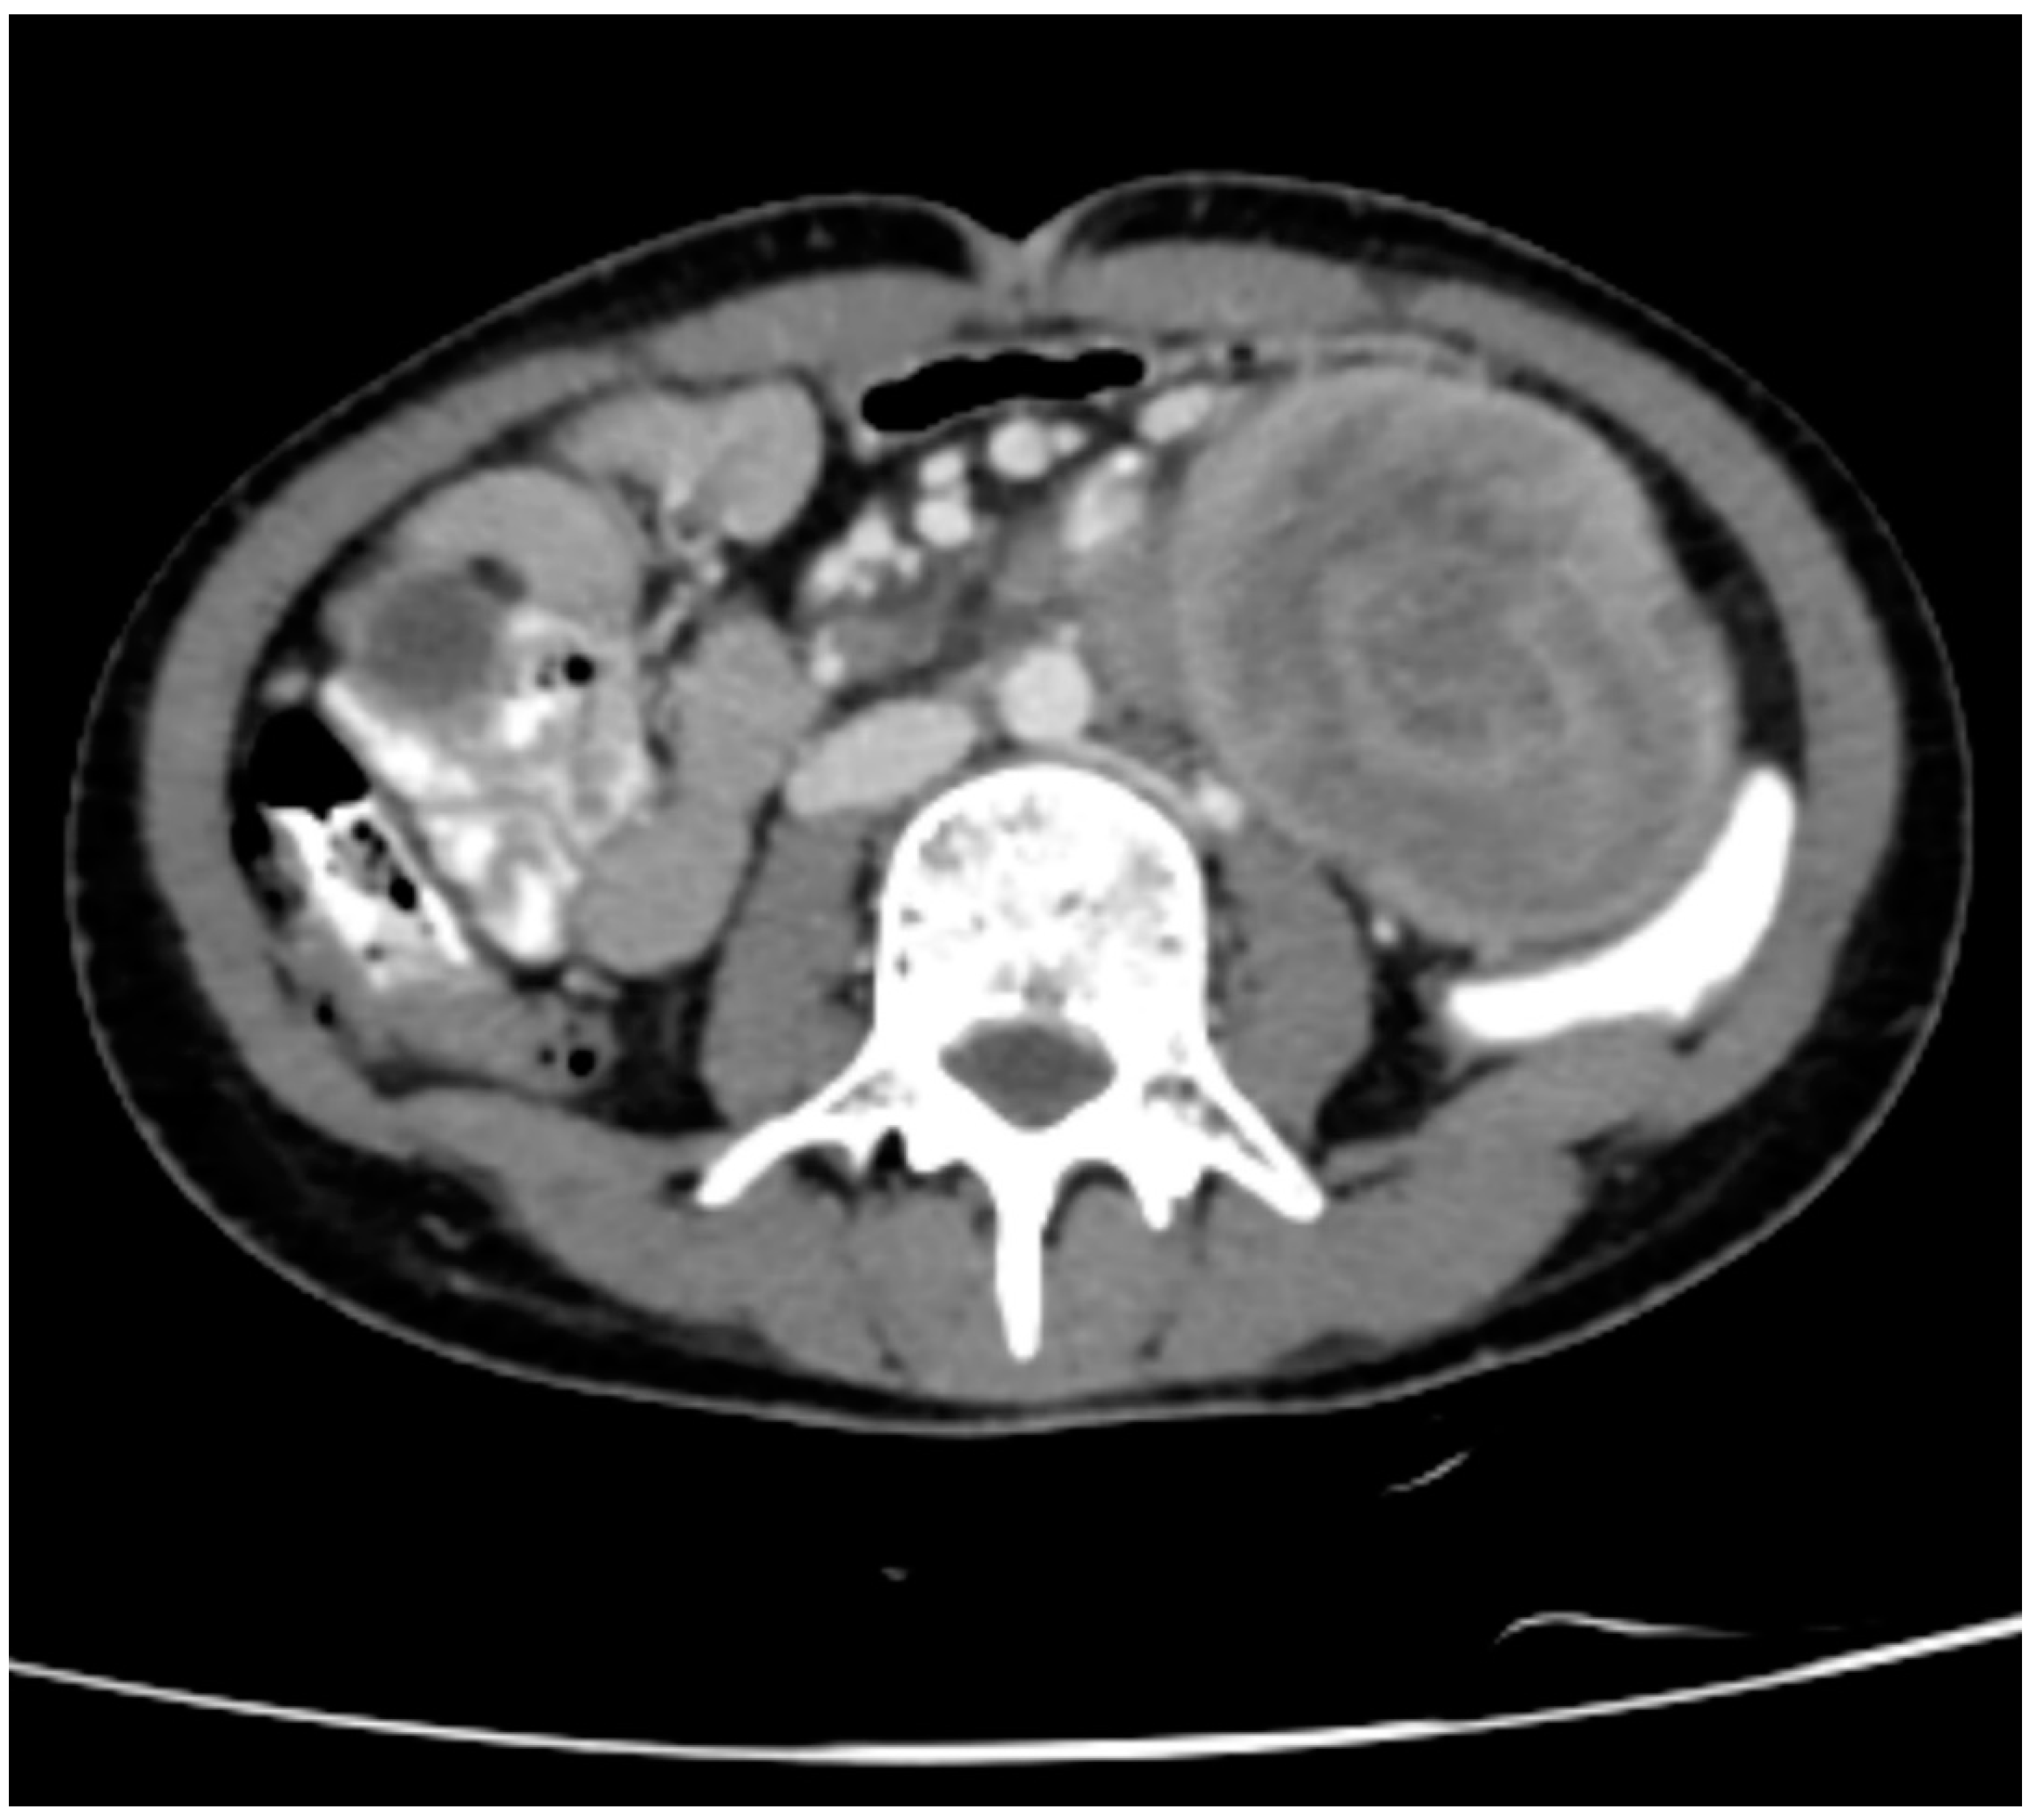

Figure 4. CT Coronal section Abdomen showing dilated common Bile Duct, Right and left Hepatic Duct and Intra Hepatic Biliary Radicles.

Proximal CBD measures 11 mm, Mid-CBD measures 8 mm, dilated. There is evidence of smooth tapering of distal CBD and opening into the ampulla of the Vater in the Intussusceptum. No evidence of any intraluminal calculus, or possibility of stricture formation secondary to intussusception.

The Intussuscipens shows enhancing reactionary wall thickening of the 3rd and 4th part of the duodenum and proximal jejunum, maximum wall thickness measures approximately 8 mm of the 4th part of the duodenum. The Intussusceptum does not show any obvious mass lesion or lead point, however underlying ampullary lesion cannot be ruled out owing to the presence of a double duct sign.